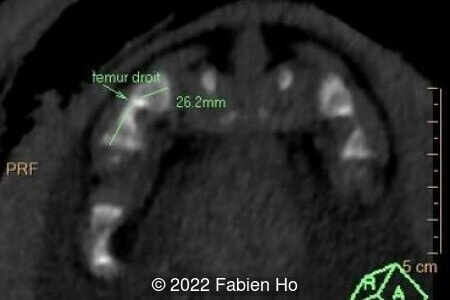

A CT scan was subsequently performed at 32 weeks gestation

The prenatal CT scan showed:

- Low bone density of skull and lower limbs

- Very short long bones with curved femurs, tibias and fibulas. The curvature of the long bones reaches a 90° angle concerning for fracture. Upper limbs are moderately curved without fracture.